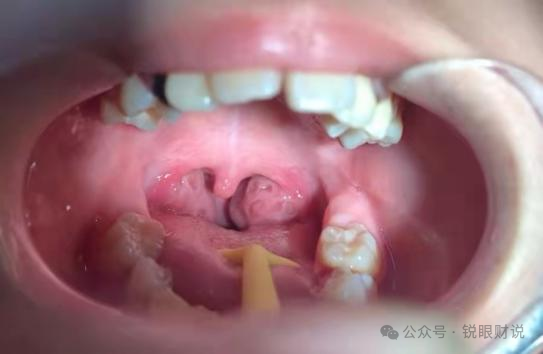

扁桃体——免疫的守门人

扁桃体,这对位于咽喉两侧的小腺体,经常被人们视为容易引发问题的器官。

每当感冒或喉咙感染时,它们往往会肿胀、发炎,给我们带来不适。然而,这并不能掩盖它们在免疫系统中的重要地位。

扁桃体是我们身体的第一道防线,它们能够识别和拦截进入呼吸道的病原体,如细菌和病毒。

通过产生抗体和免疫细胞,扁桃体能够迅速应对感染,防止病原体进一步侵入身体。

这种免疫反应不仅有助于保护我们的健康,还能为免疫系统提供宝贵的记忆,使得我们在未来遇到相同病原体时能够更快速地做出反应。

当然,如果扁桃体反复发炎、肿大,严重影响了呼吸和吞咽功能,甚至引发了其他并发症,那么医生可能会建议割除。

但在大多数情况下,保留扁桃体并对其进行适当的保养和照顾,是更加明智的选择。